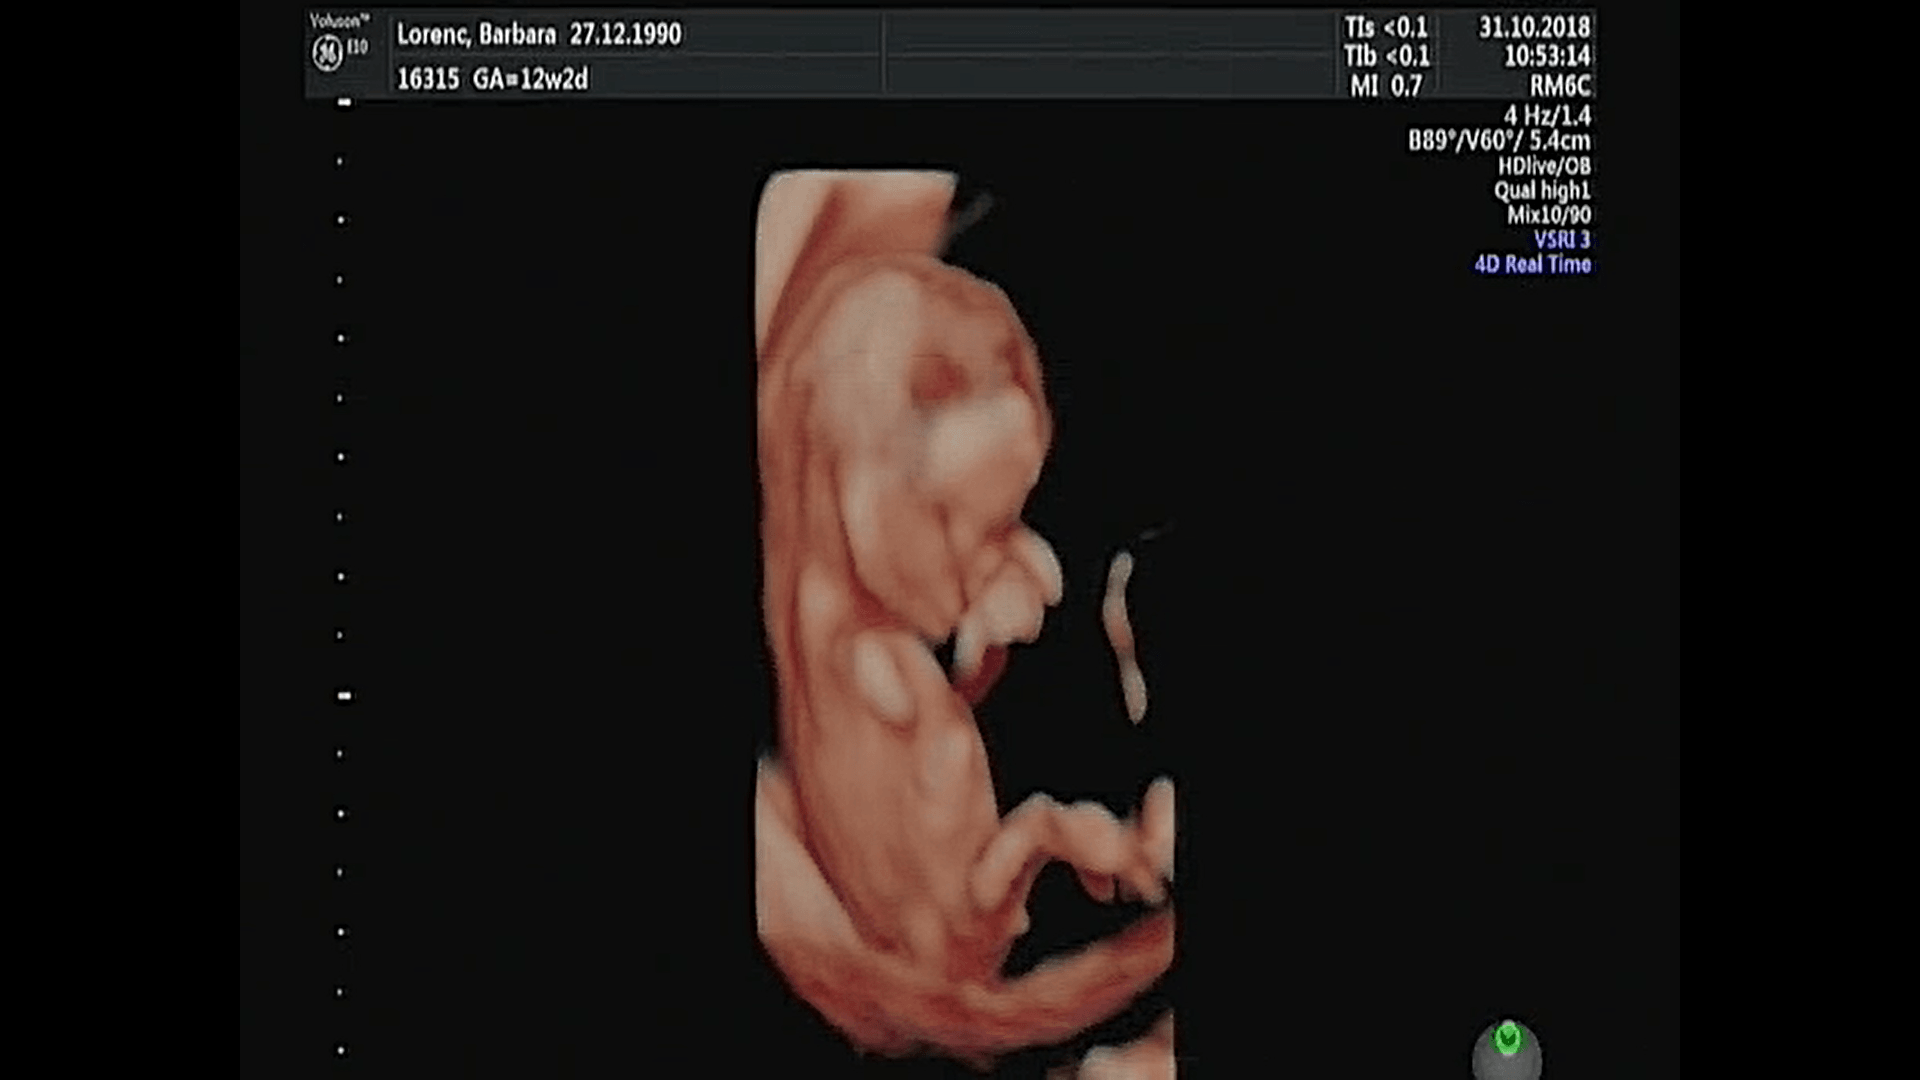

Witam w 19 tygodniu ciąży dowiedziałam się ze będę miała dziewczynkę w 20 tyg okazało się jednak , że to chłopak. Sama już nie wiem bo na jednym usg widać na pewno dziewuche a na drugim chłopca. Może to pempowina ?? Może ktoś mi pomoże rozwiązać ta zagadkę